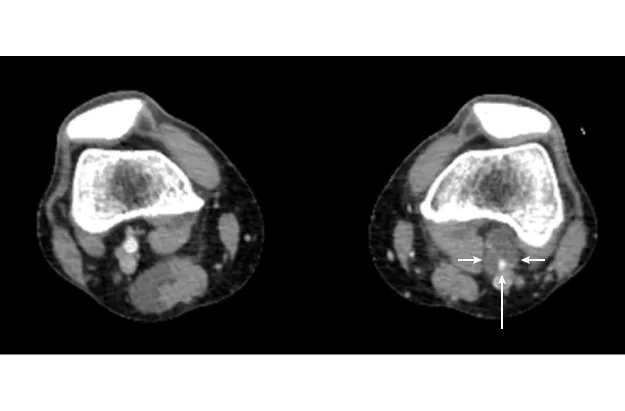

図2

図2. 左膝窩動脈外膜嚢腫の血管造影

膝窩動脈狭窄像(矢印)